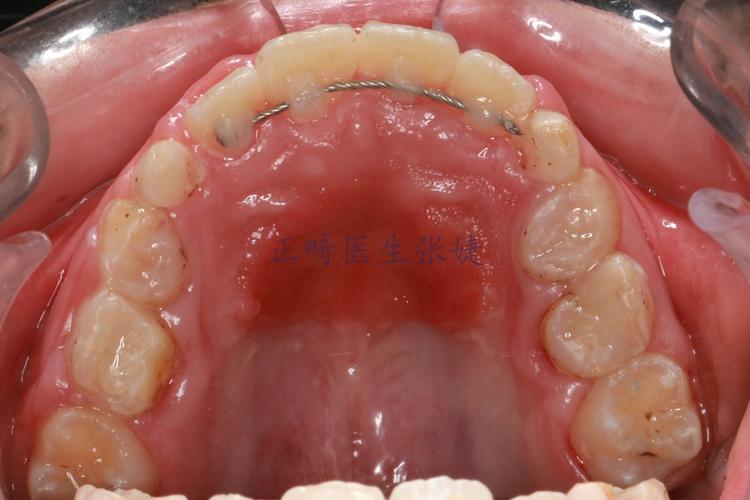

| 种植体支抗技术 | 在牙槽骨内植入微小钛钉(支抗钉),作为“移动牙齿的锚点” | 提供强大的稳定支抗,避免其他牙齿移动,实现精准控根 | 需微创植入,少数患者有异物感 | 牙齿大量前突、需要后牙前移、磨牙垂直向控制等 |